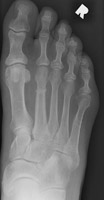

A | AP radiograph of the foot. This shows a region of periosteal new bone at the distal aspect of the second metatarsal. This corresponds to a stress fracture. |